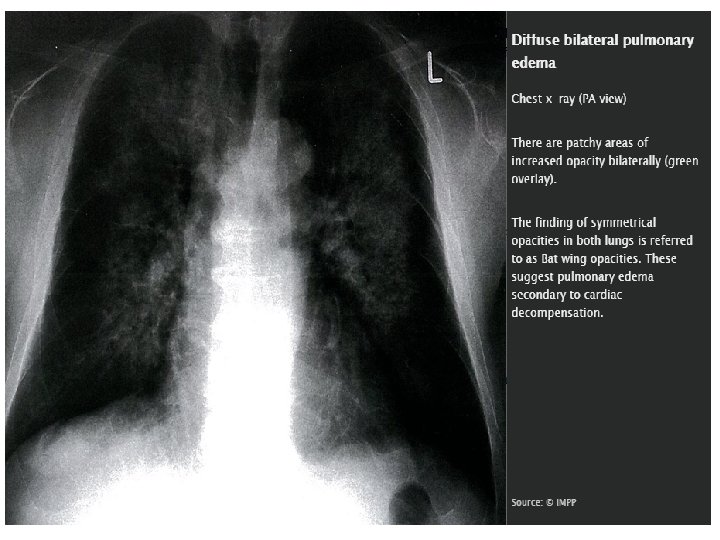

Chest x-ray Useful diagnostic tool to evaluate a patient with dyspnea and differentiate CHF from pulmonary disease Signs of cardiomegaly Cardiac-to-thoracic width ratio > 0. 5 Boot-shaped heart on PA view (due to left ventricular enlargement) Assess pulmonary congestion (see x-ray findings in pulmonary congestion)

Diagnostics • X-ray findings in pulmonary congestion • Cardiomegaly • Prominent pulmonary vessels and perihilar pulmonary edema (butterfly or “bat's wings” appearance of the hilar shadow) • Kerley B lines: visible horizontal interlobular septa caused by pulmonary edema • Basilar edema • Bilateral pleural effusions

The radiologic signs of pulmonary congestion can be remembered with “ABCDE”: A = Alveolar edema (bat's wings), B = Kerley B lines (interstitial edema), C = Cardiomegaly, D = Dilated prominent pulmonary vessels, and E= Effusions!